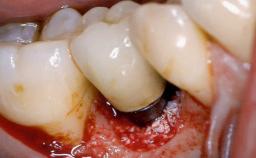

A 70-year-old female patient was referred by her general dentist to the periodontist for assessment and management of an infection associated with implant 36. The general dentist had noted suppuration on probing during examination.